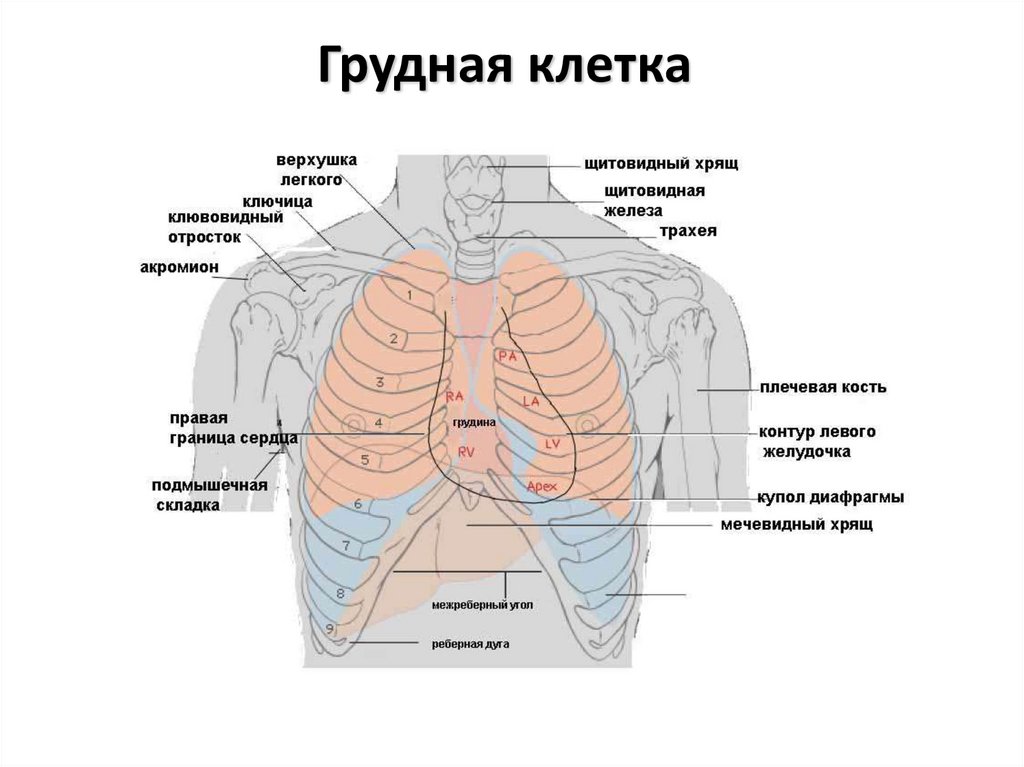

Анатомия Сердца: Расположение и Функции